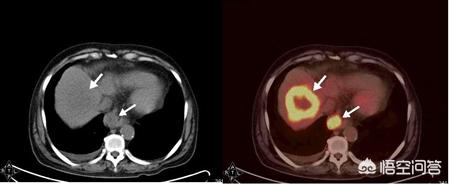

肝癌pet—ct 摄取图